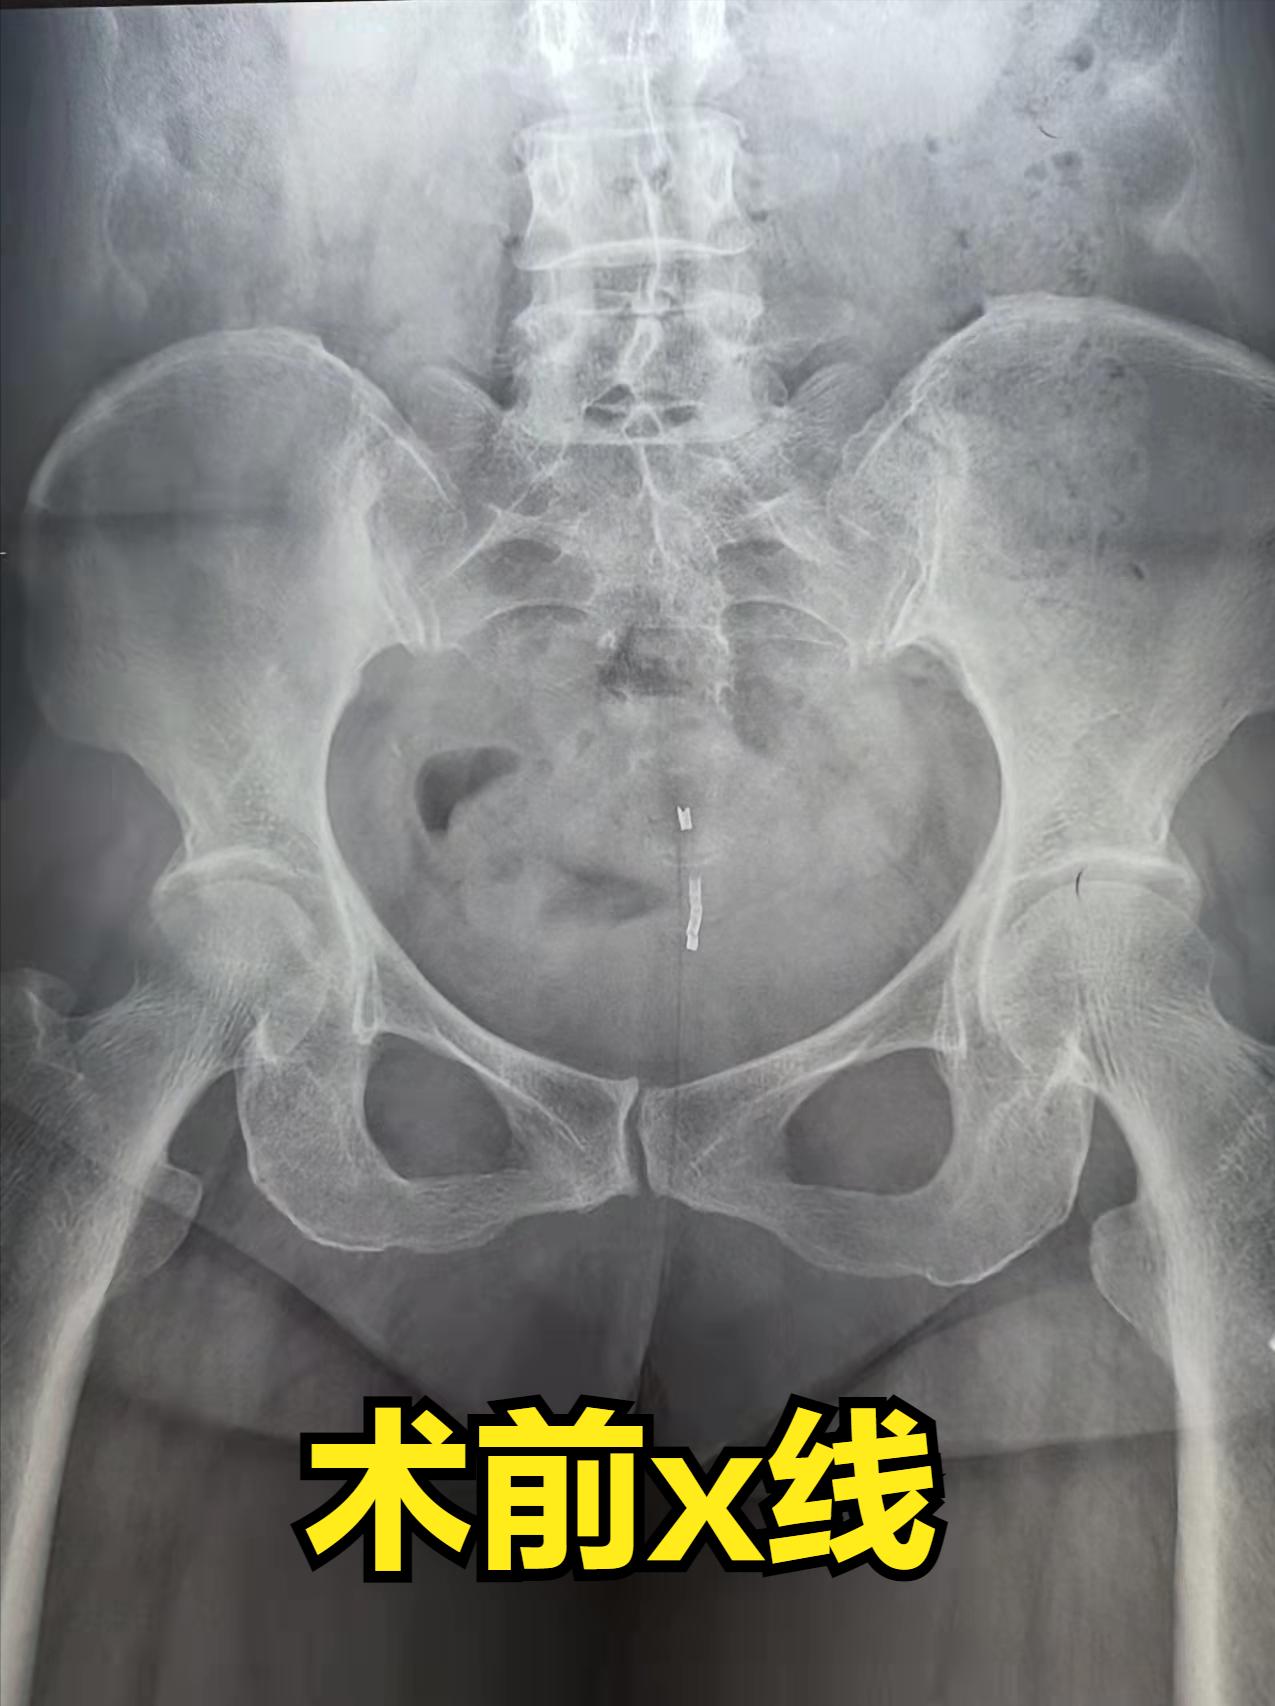

这个人上的环,按照x线片子,看着像一个吉尼环。吉尼环建议有效期是10年,理论上29年,这个人带的时间有点久,真有点担心这个像*物文**一样的环在人体内经过长时间浸泡腐蚀,即使我再小心翼翼,但是对于那个脆弱的环来说仍是摧枯拉朽之势,然后分崩离析,残留在里面又排不出来。

为了预防万一,术前我准备了宫腔镜,万一有断裂残留,宫腔镜下取一下。